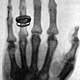

• Primera imagen de rayos X

Primera imagen de rayos X

Radiografía tomada por Wilhelm Roetgen de la mano izquierda de de Albert von Kölliker